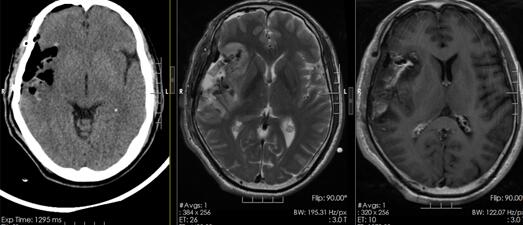

图二、病理结果((右侧额颞岛区)幕上室管膜瘤,WHOII级)

图三、术后复查,肿瘤全切除

患者目前情况:术后患者恢复好,神志清楚,言语流利,四肢肢体肌力5级,肌张力正常,1周后及出院,目前于肿瘤放疗科继续治疗,正常生活未受影响。